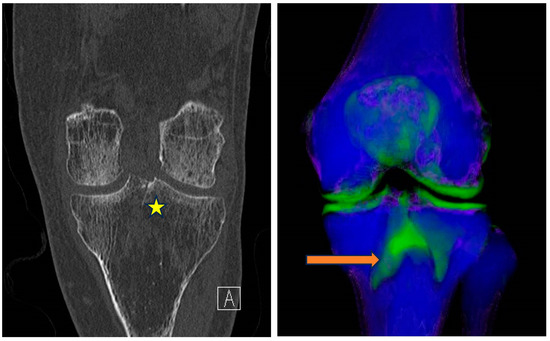

5.4.1. Bone Marrow Edema (BME)

5.4.2. Gout